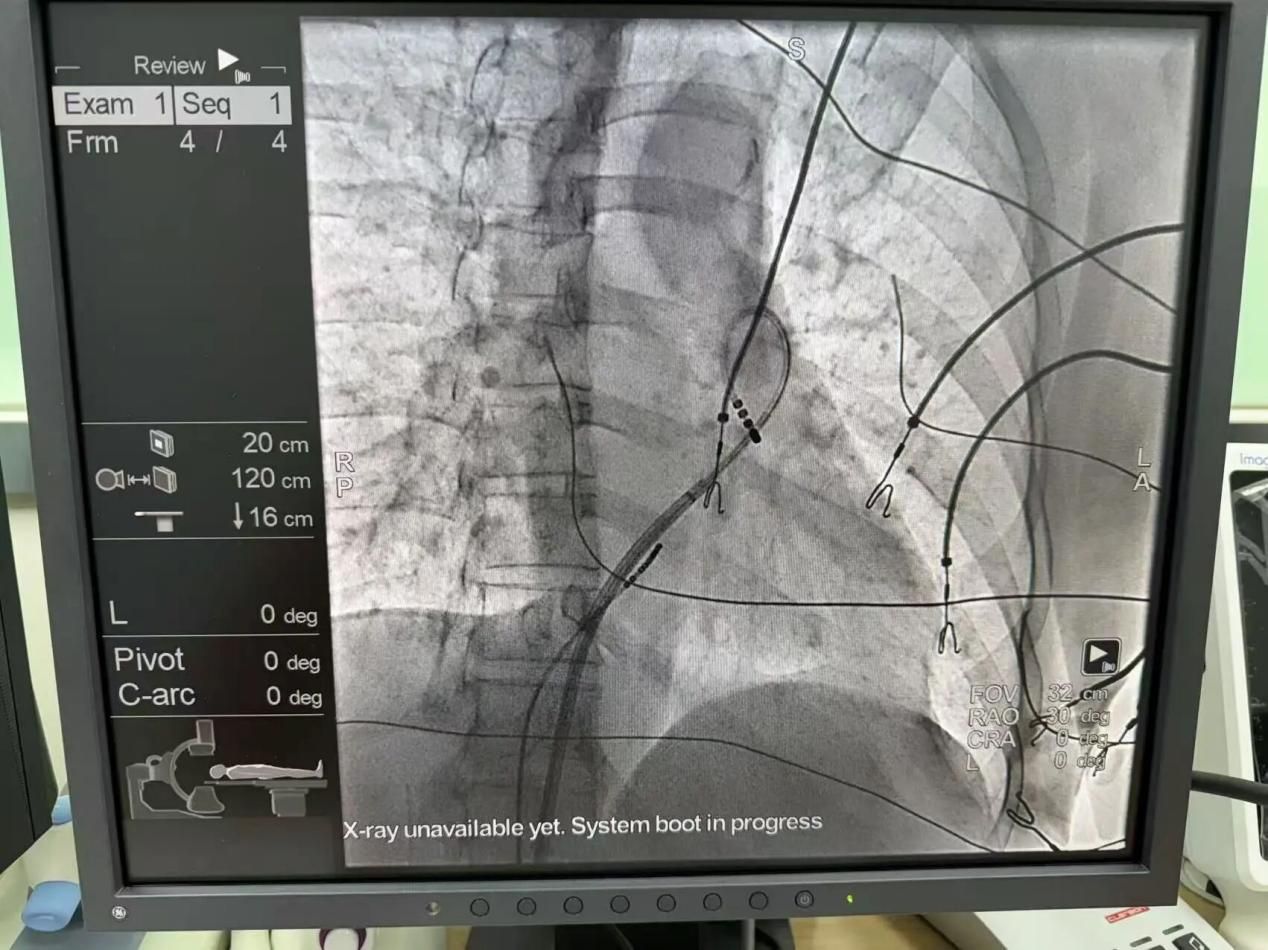

1、新疆医院成功开展首例IABP辅助治疗

近日,一名心力衰竭、休克与急性心肌梗塞交织的危重患者,新疆医院重症医学科,通过全面评估病情,启动主动脉内球囊反搏(IABP)辅助治疗,历经48小时精细监护与调整,生命体征回归平稳,标志着新疆医院在重症心血管疾病救治能力上实现了重要突破。